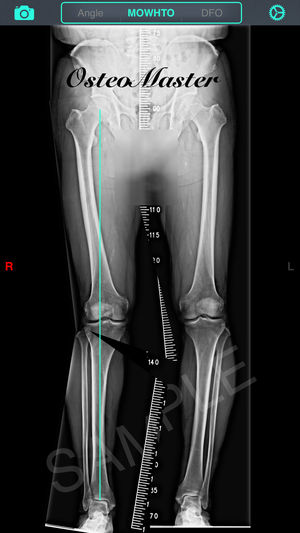

‎截骨神器 - 用于高胫骨截骨术(HTO)和股骨远端截骨术(DFO)的手术前术前规划工具。 特征: 1. 测量骨骼的解剖或力学軸角度,只需通过相机或照片库输入图像。 2. 计算术前负重线(WBL)和规划目标WBL。 3. 自动计算截骨矫正角度、楔块高度、切锯深度与脚长变化。 4. 设定期望WBL,矫正角度,缺口高度,MPTA或LDFA 5. 提供開放(open)或閉合(close)、内侧(medial)或外侧(lateral)截骨。 6. 模拟截骨调整后结果。 教学視頻:https://v.qq.com/x/page/h0527kc4vj1.html 簡体用户指南:http://pan.ba…